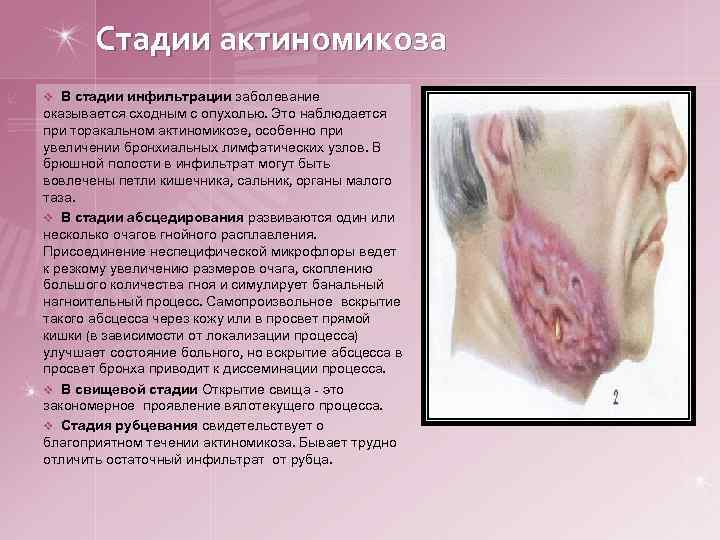

Стадии актиномикоза v В стадии инфильтрации заболевание оказывается сходным с опухолью. Это наблюдается при торакальном актиномикозе, особенно при увеличении бронхиальных лимфатических узлов. В брюшной полости в инфильтрат могут быть вовлечены петли кишечника, сальник, органы малого таза. v В стадии абсцедирования развиваются один или несколько очагов гнойного расплавления. Присоединение неспецифической микрофлоры ведет к резкому увеличению размеров очага, скоплению большого количества гноя и симулирует банальный нагноительный процесс. Самопроизвольное вскрытие такого абсцесса через кожу или в просвет прямой кишки (в зависимости от локализации процесса) улучшает состояние больного, но вскрытие абсцесса в просвет бронха приводит к диссеминации процесса. v В свищевой стадии Открытие свища - это закономерное проявление вялотекущего процесса. v Стадия рубцевания свидетельствует о благоприятном течении актиномикоза. Бывает трудно отличить остаточный инфильтрат от рубца.

Клинические формы актиномикоза 1. Актиномикоз головы, языка и шеи встречается наиболее часто. § глубокая (мышечная) форма, когда процесс локализуется в межмышечной клетчатке преимущественно в жевательных мышцах, под покрывающей их фасцией, образуя плотный, хрящевой консистенции инфильтрат в области угла нижней челюсти. Асимметрия лица, тризм. Образование свищей с гнойным или кровянисто-гнойным отделяемым с примесью друз. § подкожная форма. § кожная форма. При кожной форме актиномикоза инфильтраты шаровидные или полушаровидные, локализующиеся в подкожной клетчатке. Тризма и нарушений процессов жевания не наблюдается. Кожная форма встречается редко.

Рис. 1 Синюшность кожи вокруг свищей.